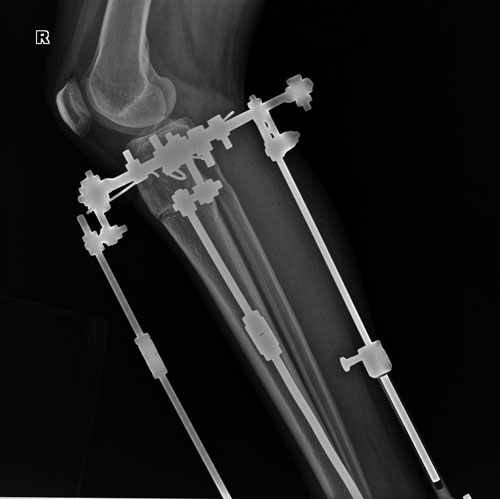

Дата операции 01.06.2018г.

Дата снятия аппаратов 29.08.2018г.

Срок сращения 88 дней.